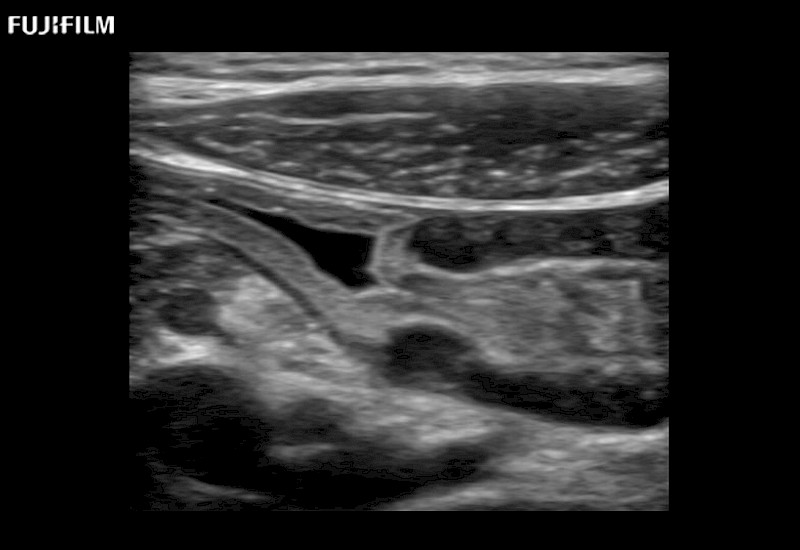

The ARIETTA 750 incorporates all of the proven technologies and functions that medical professionals have come to expect from Fujifilm Healthcare.

ARIETTA 750 is the definitive diagnostic ultrasound solution for any clinical setting - Private Office, Imaging Center, or Hospital. The ARIETTA platform provides the ultimate in clinical performance with its state-of-the-art features and large user-friendly display.

The ARIETTA 650 DI combines trusted Fujifilm Healthcare technologies and features tailored for surgical oncology.

Designed to meet the demands of surgeons, the ARIETTA 650 DI offers precise guidance. Its advanced capabilities and large, intuitive display offer accurate and efficient care in operating rooms and specialized surgical settings.